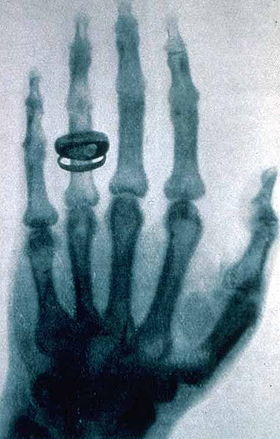

X-ray by Wilhelm Röntgen of Albert von Kölliker's hand - 18960123-02.jpg

X-ray of a hand. X-rays are a common medical test.